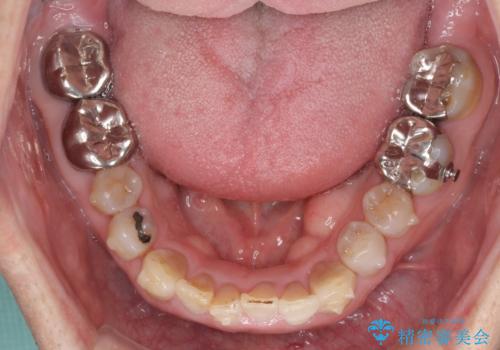

上顎の狭窄歯列 インビザラインによる拡大矯正

- 前歯の叢生と臼歯のクロスバイトを気にして来院された患者様です。

急速拡大装置による上顎の側方拡大を行い、その後はインビザラインより歯列を改善することとしました。

20代後半以降の男性は上顎骨の側方拡大処置の成功率が低く、今回も骨を拡大することができませんでした。

しかしながら、歯列を側方に拡大することができ、その後はインビザラインにて叢生を解消することができました。